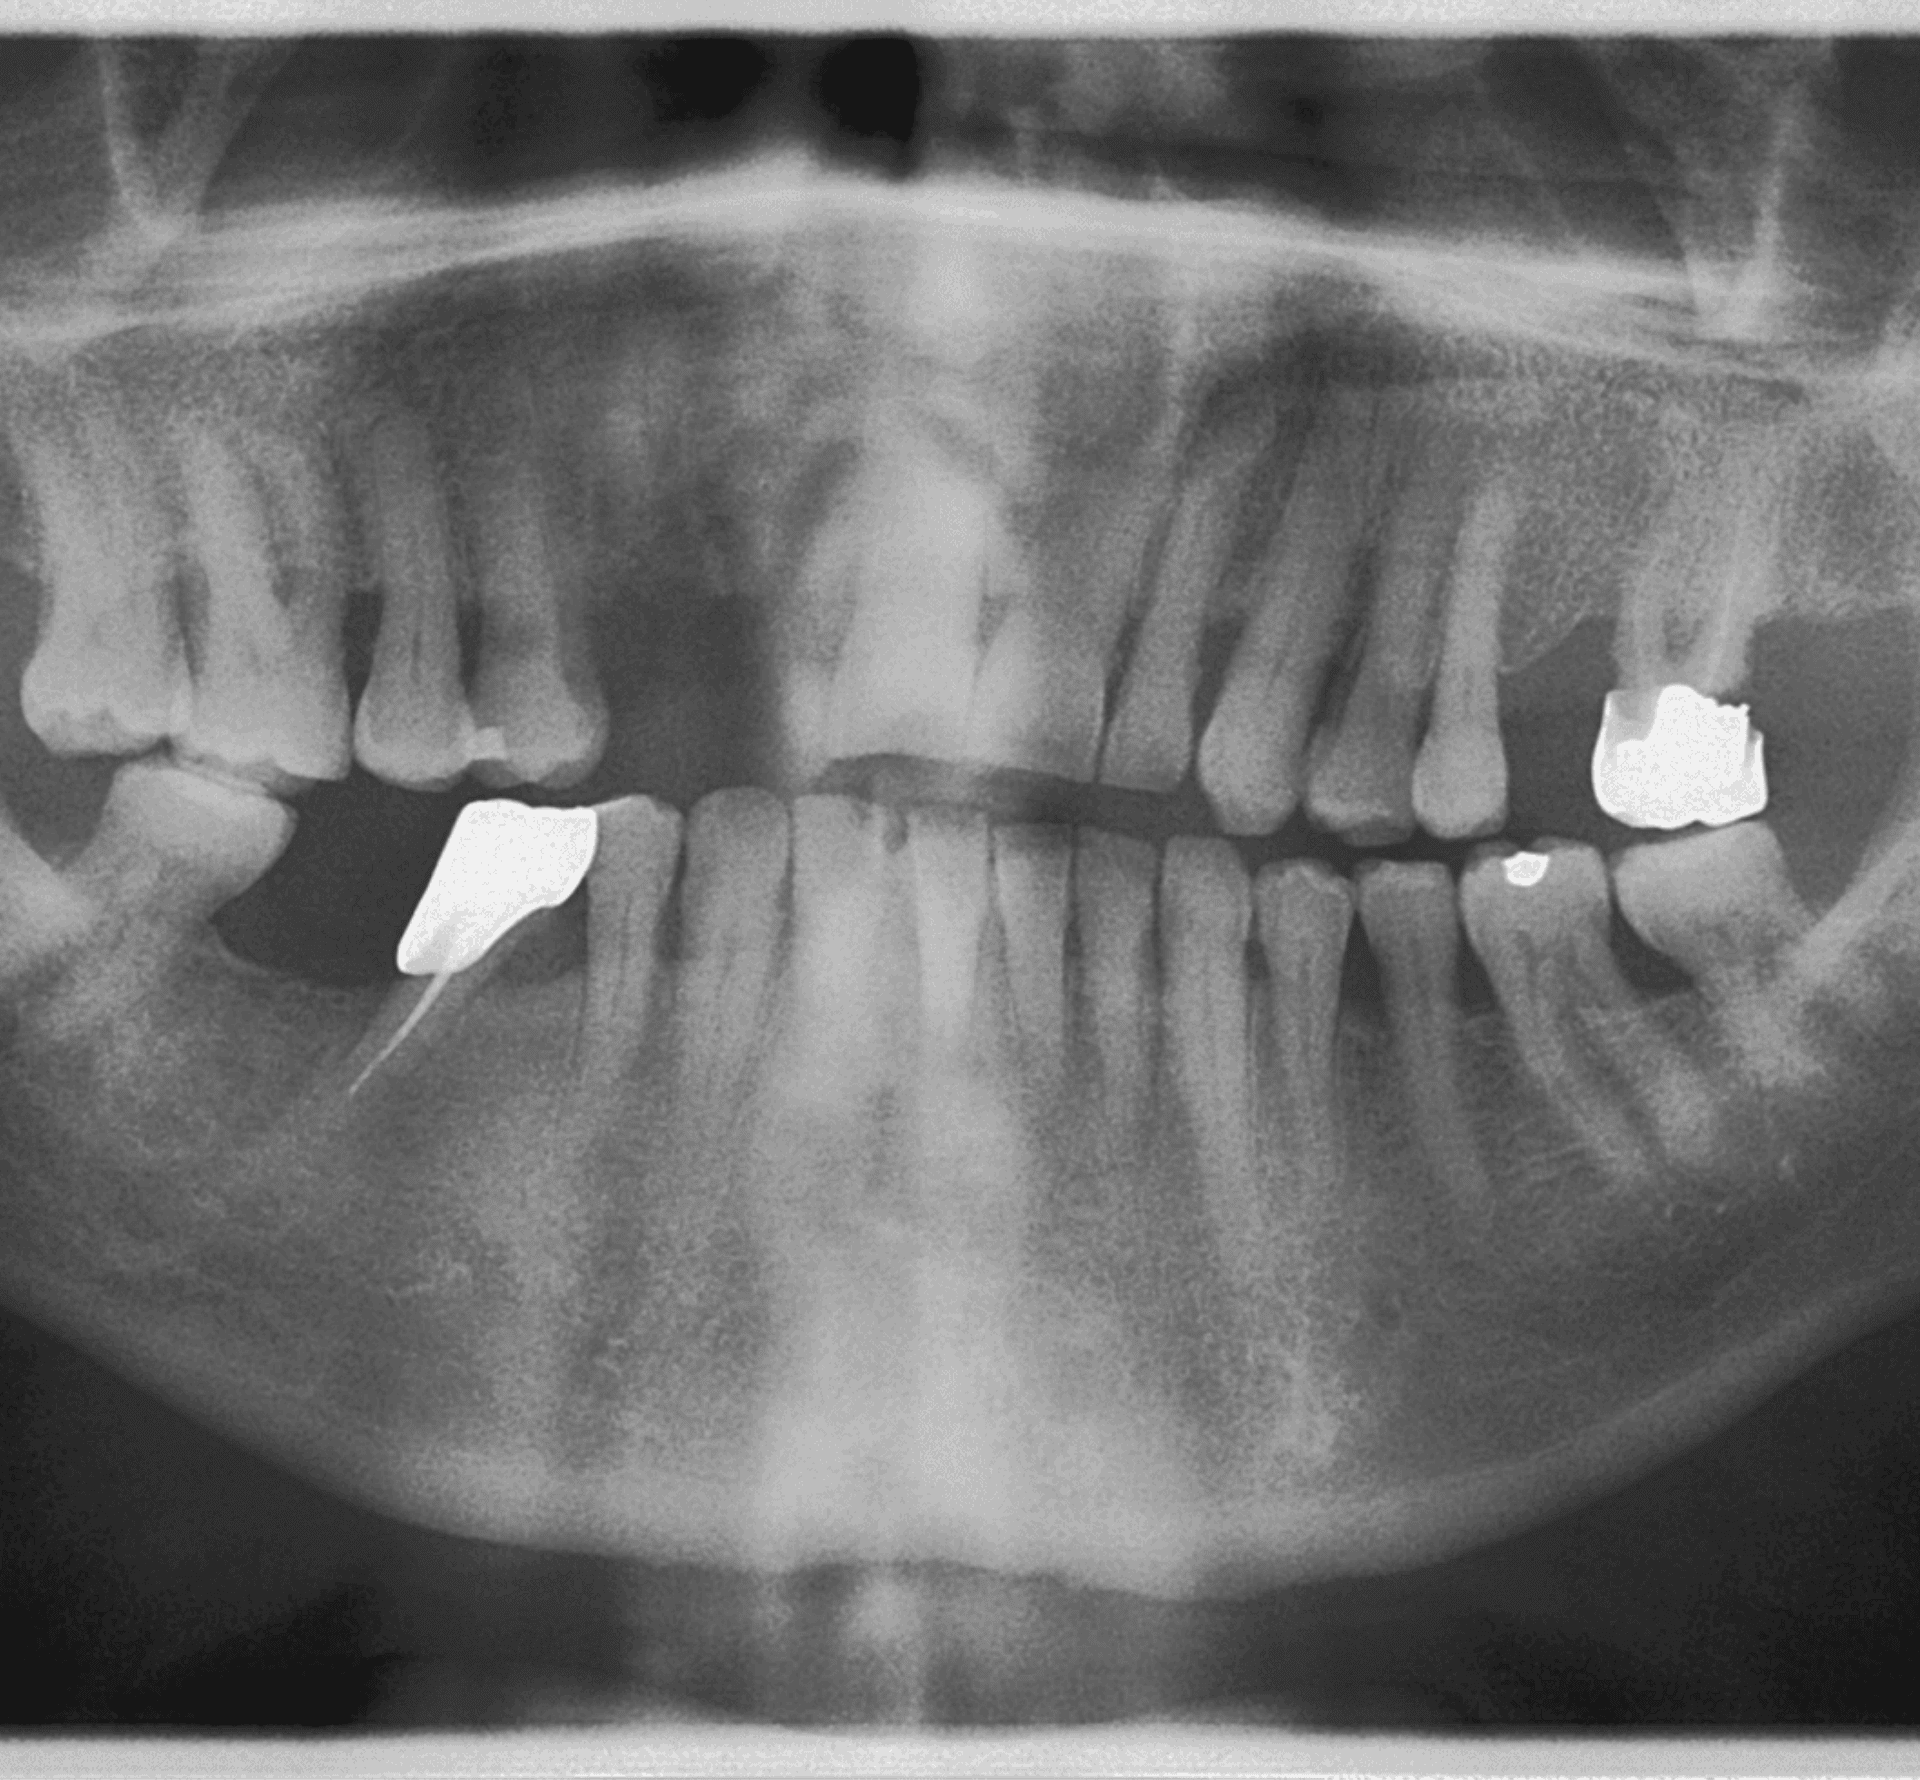

Panoramique et cone beam